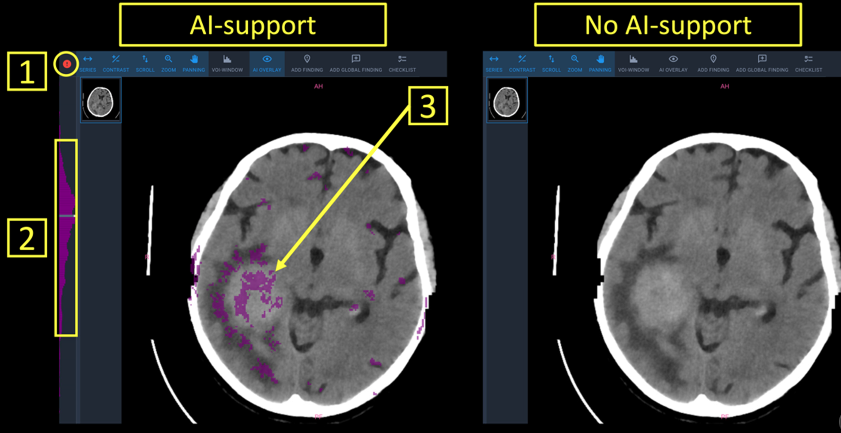

Anomaly detection in MRI images

It is designed to detect anomalies in medical imaging with high precision.

Using a powerful ensemble of state-of-the-art segmentation and classification deep-learning models, the system analyzes MRI scans to identify structural abnormalities across various organs.

The solution produces pixel-level segmentation masks, highlights regions of concern, and classifies detected anomalies—helping radiologists accelerate diagnosis, reduce oversight errors, and improve clinical decision-making.